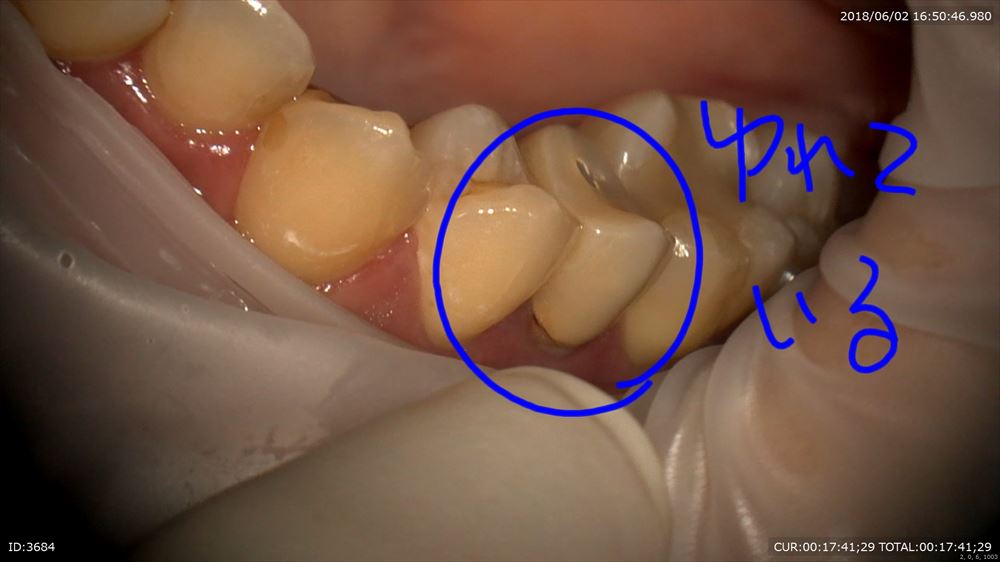

この方は他院で抜歯といわれ納得いかず来院。

マイクロスコープは動画で説明できるメリットがあります。

歯根破折なので私の診断も抜歯でした。

きちんと動画で説明。

揺れている原因は

このように

歯根ごと折れて

2本ヒビがはいっています。